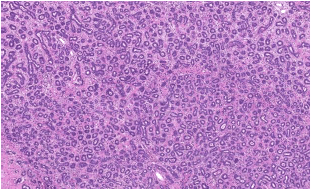

A presença desta pequena coleção de células ilustrada na imagem abaixo tem relação com . Assinale a alternativa que preencha corretamente a lacuna.

Mulher, 20 anos, com nódulo palpável na mama esquerda. Assinale a alternativa que apresenta o diagnóstico que a figura abaixo ilustra.